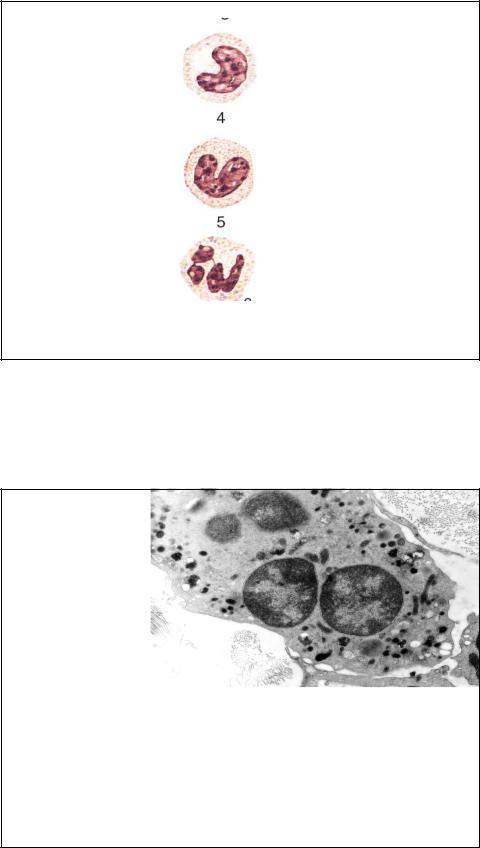

СОЗРЕВАНИЕ НЕЙТРОФИЛОВ |

Незрелые |

Нейтрофильный метамиелоцит |

нейтрофилы, |

0-0.5% |

кровоток имеют ядро в |

виде |

подковы |

(палочкоядерные |

клетки). Увеличение их |

доли |

является |

Палочкоядерный нейтрофил |

показателем |

омоложения |

3-5% |

нейтрофилов, |

вызванное чаще всего |

бактериальной |

инфекцией. |

Если |

Сегментоядерный нейтрофил |

нейтрофила 5 и более |

долей |

ядра. |

40-70% |

называется |

гиперсегментирован- |

ным и |

чаще всего |

является старым.